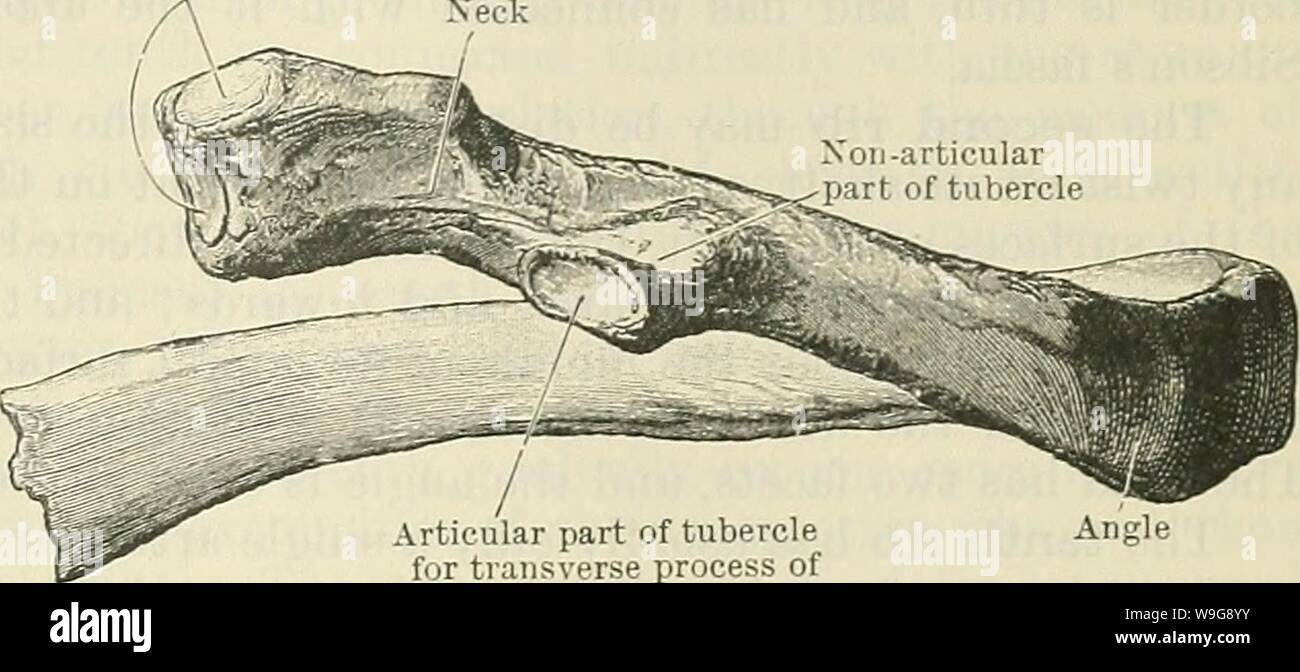

RMW9G8YY–Immagine di archivio da pagina 144 di Cunningham il libro di testo di anatomia (1914). Cunningham il libro di testo di anatomia cunninghamstextb00cunn Anno: 1914 ( le nervature. Ill sfaccettature sulla testa Xeck Xon-articolare parte del tubercolo parte articolare del tubercolo per processi trasversali delle vertebre Fig. 124.-quinta costola destra come visto da dietro. attrezzatura per esterni ed interni dei muscoli intercostali rispettivamente. Sul pavimento della scanalatura può essere visto anche le aperture dei canali per la trasmissione delle navi di nutrienti che sono orientati verso la estremità vertebrale della nervatura. La sezione anteriore o extremi sternale

RMPFYCG2–. Cunningham il libro di testo di anatomia. Anatomia. Parte articolare del tubercolo per processi trasversali delle vertebre Fig. 124.-quinta costola destra come visto da dietro. attrezzatura per esterni ed interni dei muscoli intercostali rispettivamente. Sul pavimento della scanalatura può essere visto anche le aperture dei canali per la trasmissione delle navi di nutrienti che sono orientati verso la estremità vertebrale della nervatura. La sezione anteriore o estremità sternale dell'albero, spesso leggermente ingrandita, visualizza un ovale allungata buca in cui la cartilagine costale è affondato. Nervature peculiare.-Il primo, il secondo, decimo e undicesimo di

RMPFYCG4–. Cunningham il libro di testo di anatomia. Anatomia. Le nervature. Ill sfaccettature sulla testa Xeck Xon-articolare parte del tubercolo. Parte articolare del tubercolo per processi trasversali delle vertebre Fig. 124.-quinta costola destra come visto da dietro. attrezzatura per esterni ed interni dei muscoli intercostali rispettivamente. Sul pavimento della scanalatura può essere visto anche le aperture dei canali per la trasmissione delle navi di nutrienti che sono orientati verso la estremità vertebrale della nervatura. La sezione anteriore o estremità sternale dell'albero, spesso leggermente ingrandita, visualizza un ovale allungata abisso nel quale le carti costiera